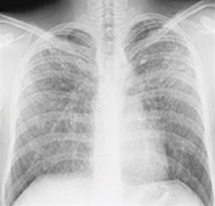

Lunger, røntgen, sarkoidose stadium IV

Stadium IV sarkoidose.